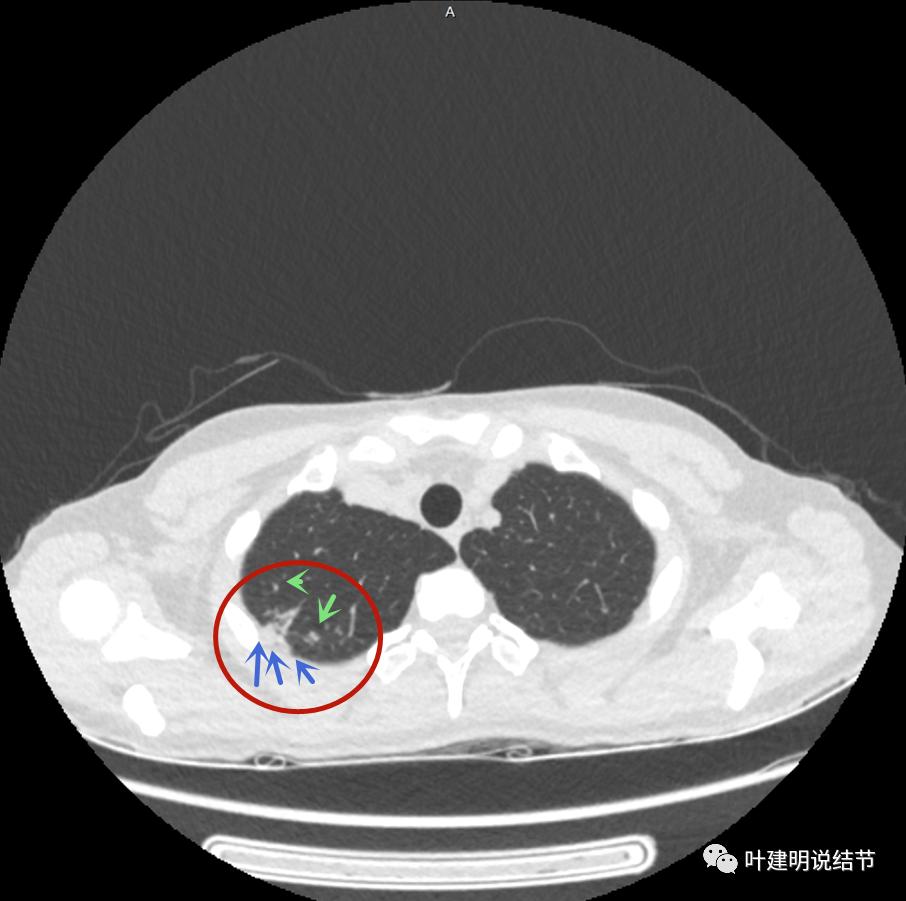

邻近有卫星灶(绿色箭头),主病灶密度过高(粉色箭头),旁边有磨玻璃影,散且模糊(砖色箭头)

邻近胸膜有增厚(蓝色箭头),主病灶边缘较为平直,缺乏膨胀性(桔色箭头),实性部分密度过高(粉色箭头),旁边有磨玻璃影,散且模糊(砖色箭头)

病灶边缘较为平直,膨胀性不足(桔色箭头)